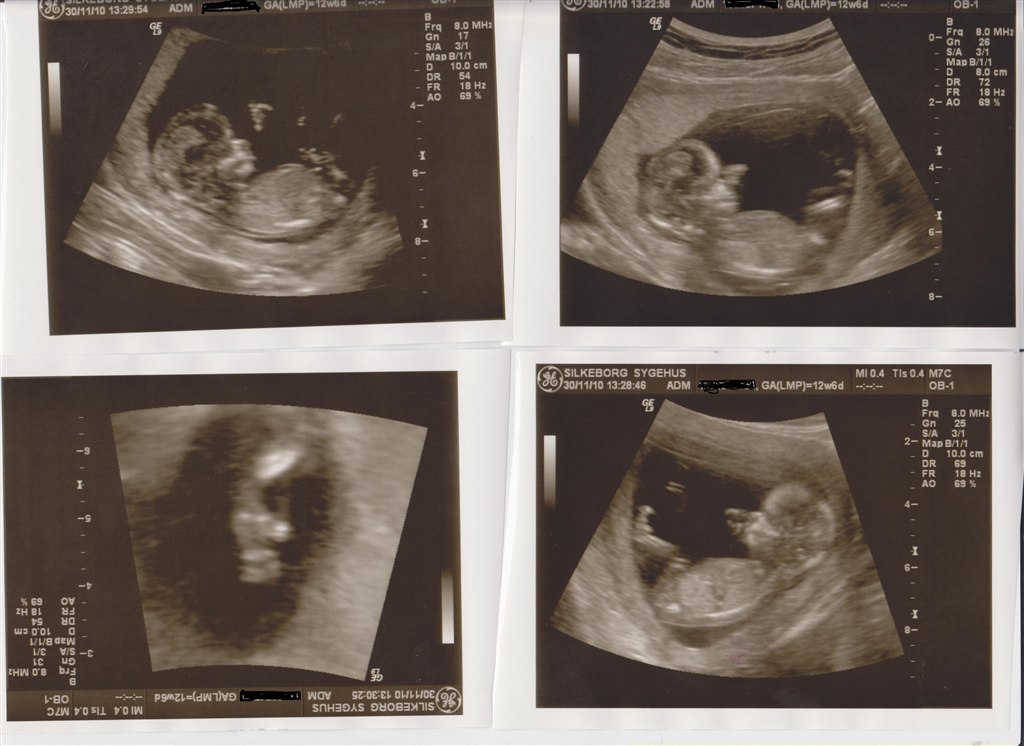

Så blev det ski min tur til at komme til NF scanning. Alt så rigtig godt ud. Chancen for mongolisme er 1 : 20322 så jeg er så glad....

Min termin bliver ikke rykket den har jeg regnet rigtig ud så ja jeg er stadig 12,6 i dag..

Den bette er 6.3cm fra hovede til numse. Og ca 12 cm fra hovede til fod.

Det er en rigtig spilopmager der er derinde. Hold da op der var gang i den inde i maven.. arme og ben boksede derud af.

Og så var vi så heldige og opleve at se den bette drak noget af fostervandet.. det så virkelig sjovt ud.

og ja ikke mindst det der fik tårende til at trille ned af kinderne af glæde, så hørte vi hjertelyden. hold da op nogen følelser der strømmede igennem kroppen..

Vedhæftede fotos (klik for at se i fuld størrelse)